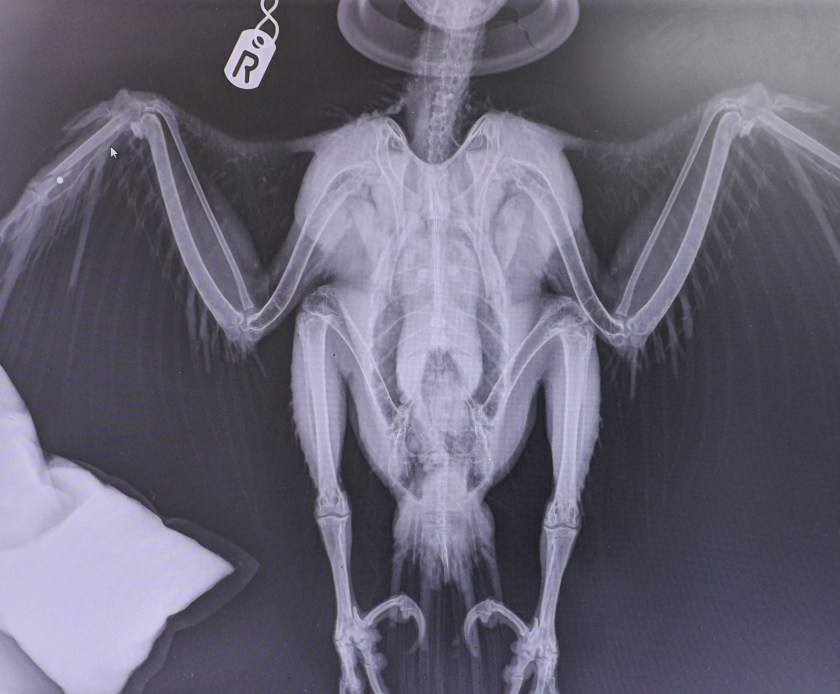

A critically-injured peregrine has been euthanised after an x-ray revealed a shotgun pellet lodged in its wing, causing a catastrophic break.

The wounded bird was taken to Vale Wildlife Hospital near Tewkesbury, Gloucestershire today. There are no further details yet about where this illegally-shot peregrine was picked up.

Assuming from the x-ray -the small white circle is the pellet lodged at the point of the wing break-then please explain what other ammunition has this profile, if it’s not a shot gun pellet?

Also don’t forget that when a shotgun is fired- the pellets from the cartridge disperse on leaving the barrel. The further from the gun the wider the spread of pellets both both laterally and longitudinally.

Your ballistic claims are only in part correct and largely an irrelevance because with so many possibilities of ‘chance’ and corruption there is clearly no irrefutable evidence. The bird in the x/ray – unlikely the same bird as in the photograph with feathers, appears to have one piece of shot beside a broken Metacarpal bone. The photograph on the wing of the bird with blood showing, is in a deferent position to that of what may be lead shot.

I previously asked who it was who killed the bird, it being claimed that it was alive when it was found. It would also be interest to know of the roll of the person who killed the bird, assuming that it was a different person than the one who performed the x/ray. The major wing bones, the Humerus, the Ulna and the Radius remain undamaged, and I’ve previously requested to have it explained, why the bird was killed – when there was simply no need. Damaged Metacarpals repair readily and with appropriate treatment, the bird could at least have been given the chance to repair and then be given its freedom. There may be those who consider that the person who finally ended the life of the bird was as culpable as the person who, it’s claimed, shot it.

We haven’t been told the medical reasons as to why it was decided not attempt a repair on the wing- there is some clue that the pellet was lodged in the wing, and it may have been decided that with the shock the bird will have suffered, along with the injuries, that putting the bird under anaesthetic in order to operate and remove the pellet was likely to result in death? But that is something only the vet who assessed the bird will know-and we aren’t provided with that information.